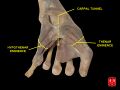

The carpal bones that make up the wrist form an arch which is convex on the dorsal side of the hand and concave on the palmar side. The groove on the palmar side, the sulcus carpi, is covered by the flexor retinaculum, a sheath of tough connective tissue, thus forming the carpal tunnel. On the side of the radius, the flexor retinaculum is attached to the scaphoid bone, more precisely its tubercle, as well as the ridge of trapezium. On the ulnar side, it is attached to the pisiform and hook of hamate.[4]

The tendons of the flexor digitorum superficialis and profundus pass through a common ulnar sheath, while the tendon of the flexor pollicis longus passes through a separate radial sheath. The mesotendon shared by these tendons is attached to the radial and palmar walls of the carpal tunnel.[4]

Superficial to the carpal tunnel and the flexor retinaculum, the ulnar artery and ulnar nerve pass through the ulnar tunnel/Guyon's canal.[4]

Ten structures pass through the carpal tunnel, most of them flexor tendons[2] (not the muscles themselves):

- flexor digitorum profundus (four tendons)

- flexor digitorum superficialis (four tendons)

- flexor pollicis longus (one tendon)

- Median nerve between tendons of flexor digitorum profundus and flexor digitorum superficialis

The flexor carpi radialis (one tendon) is often incorrectly stated to travel within the carpal tunnel. More precisely, it travels within the fibers of the flexor retinaculum which forms the roof of the carpal tunnel, rather than running inside the tunnel itself.